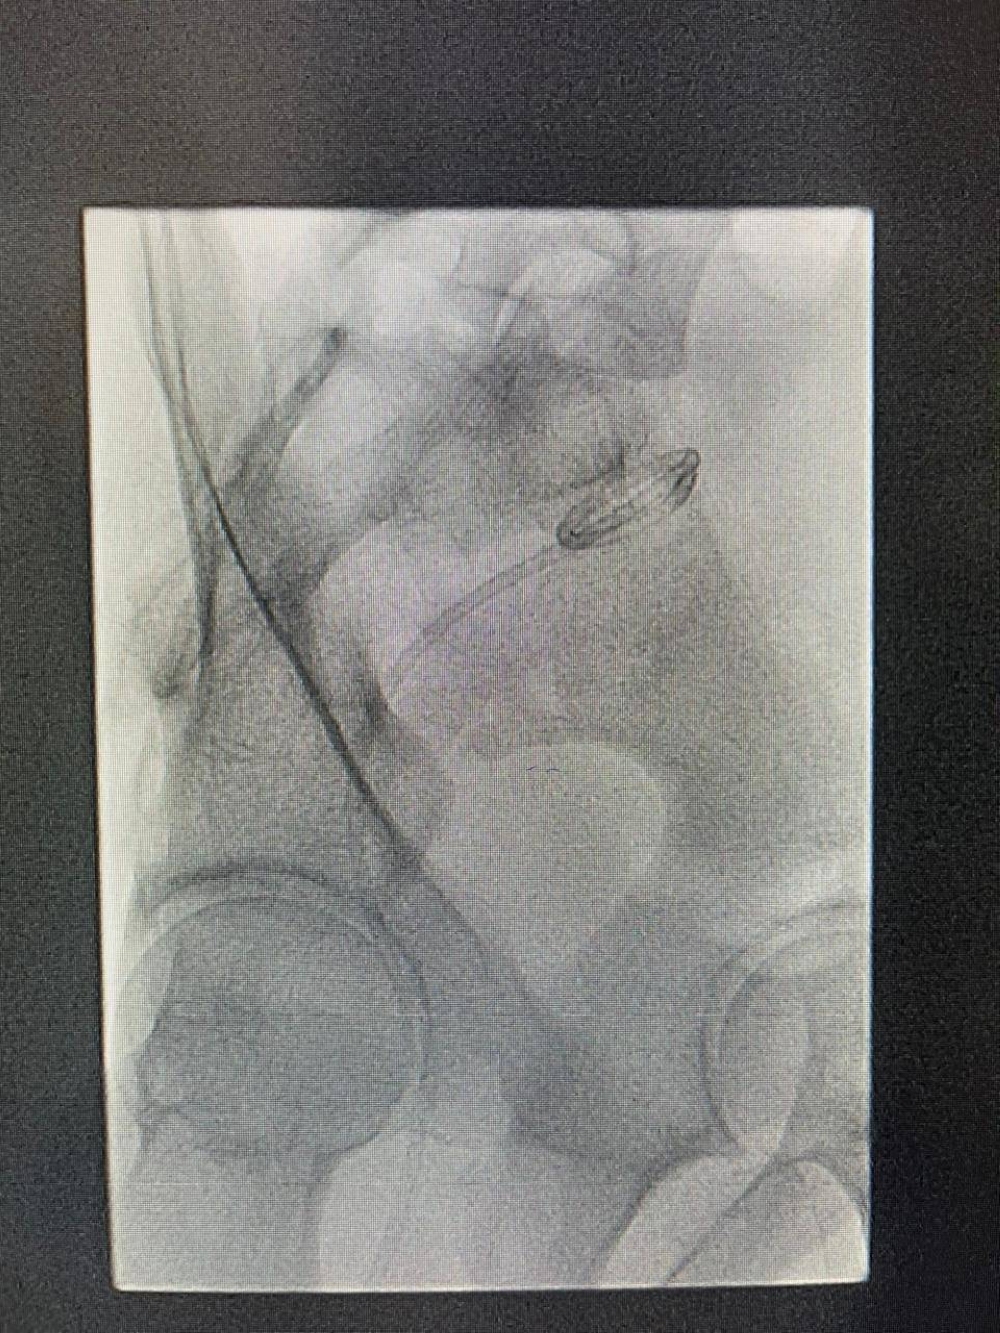

نجح فريق الأشعة التداخلية في مستشفى الأمير محمد بن عبدالعزيز أحد مكونات تجمع الرياض الصحي الثاني في إجراء قسطرة باستخدام الأشعة التداخلية والأشعة الصوتية لمريض يُعاني من تجمع صديدي في منطقة معقدة في قاع الحوض بين المستقيم و المثانة لمريض يبلغ من العمر 38 عاما.

وذكر أن الحالة دعت الفريق الطبي إلى ضرورة إجراء قسطرة باستخدام الأشعة التداخلية والأشعة الصوتية من خلال تخدير موضعي؛ لافتا إلى أن التأخير في التدخل الطبي قد يُسبب حدوث تسمم بالدم.

وأبان أن الفريق الطبي استطاع سحب التجمع الصديدي الموجود في قاع الحوض مجنباً المريض من عملية جراحية بالغة التعقيد قد تستغرق 6 ساعات.